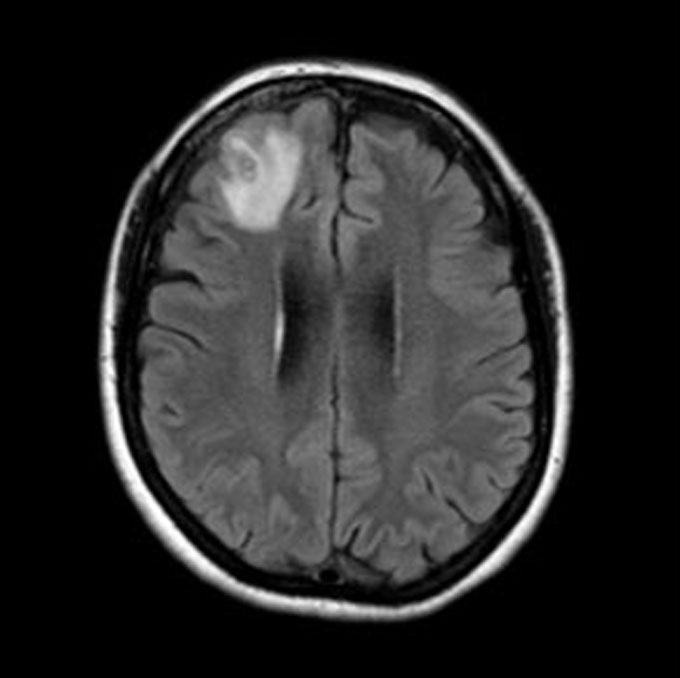

A second clue came months later. The woman became forgetful and depressed. Fortunately, a physician noticed something was off and ordered an MRI scan of her brain. It turned up a ghostly glow in her right frontal lobe.

That glow could mean different things, says Sanjaya Senanayake. He’s an infectious disease physician at the Australian National University and the Canberra Hospital. The spot could have been cancer. Or maybe a pocket of pus. “No one thought it was going to be a worm,” he recalls.